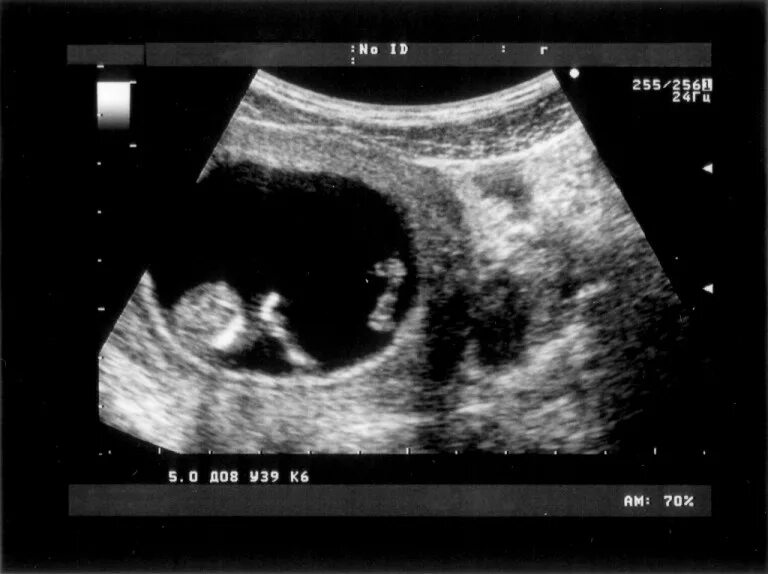

На какой недели можно увидеть плод